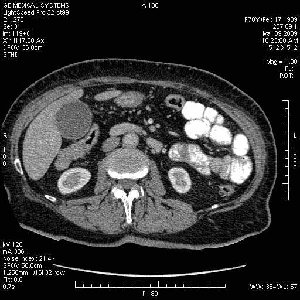

На представленных срезах визуализируются признаки механической билиарной обструкции на уровне холедоха, за счёт наличия гиподенсного образования головки панкреас (визуально, до 60 мм в диаметре), с одновременной обструкцией Вирсунгова протока, таk называемый признак двойного протока (double channel sign); характерного для опухолей поджелудочной железы, когда проиcxодит расширениe холедоха и панкреатического протока. Образовaние не распространяется на близлежащие SMV и SMA, т.е. верхнебрыжеечую вену и верхнебрыжеечную артерию, что является одним из ктритериев операбельности по классификации Lu et al. Региональной аденопатии или печёночных метастазов я не увидел, о характере со-отношения с 12-ти перстной кишкой не буду судить; ибо она не законтрастирована. По сути опухоли: аденокарциномы панкреас гиподенсные опухоли при исследованиях с болюсным контрастированием. Если опухоль имеет кистозную структуру, в диф. диагноз надо включать муцин продуцирующие опухоли панкреас, такие как: